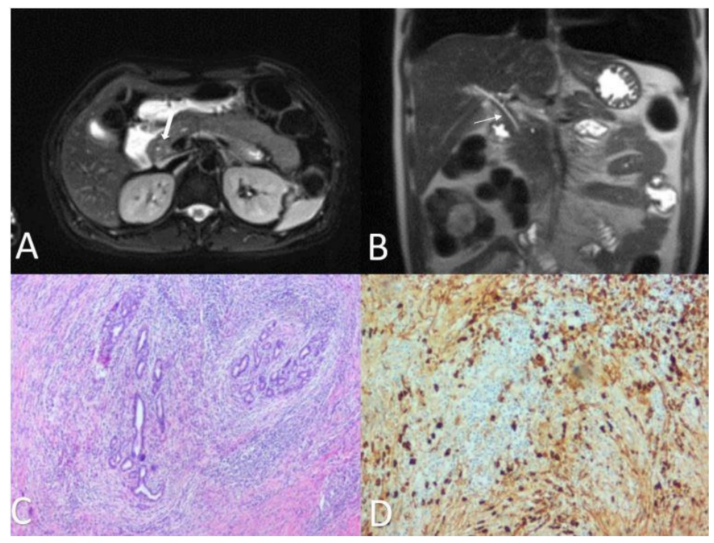

实验室检查方面,血清IgG4水平升高是IgG4-SC的重要特征,但不能单独依据血清IgG4升高诊断IgG4-SC。病理诊断方面,指南推荐病变组织中IgG4阳性浆细胞>10个/HPF,同时IgG4/IgG阳性浆细胞比例>40%(图5)。

图5.IgG4-SC病理特征

(源自讲者幻灯)

然而,血浆IgG4水平正常时亦被忽略,不能完全除外IgG4相关疾病。据最新病例[22]报道,血浆IgG4水平正常、胰腺组织未受累;MR提示胆管向心性增厚;肝脏病理可见大量浆细胞、IgG4阳性细胞浸润。

图6.IgG4-SC病例影像学与病理特征